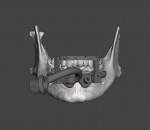

The laboratory technician then imported the CBCT data into the dynamic navigation treatment planning software (X-Guide, X-Nav Technologies). The intraoral scans were aligned with the CBCT data, and the dental implants were planned in a restoratively driven manner. The virtual treatment plant was then exported from the software and imported into dental CAD software (DentalCAD, exocad). The technician designed the provisional prosthesis, and the implants were verified to be in suitable positions. Using a combination of other CAD software modules, the technician designed a foundation guide, occlusal positioning jig, and provisional prosthesis. The foundation guide included an attachment arm for the dynamic navigation patient tracker array (Figure 1). The foundation guide was designed to allow its superior edge to act as a bone reduction reference and two-guide tube for fixation screws. The fixation screw positions were designed to not intersect with the planned implant positions. The position of the attachment arm was designed with input from the surgeon to help prevent an obstructed view of the overhead stereotactic cameras during the procedure.

At surgery, the overlying mandibular buccal mucosa was reflected in a full thickness manner. The occlusal positioning device/foundation guide was seated and verified to be in correct position (Figures 2 and Figure 3). Fixation screws were placed to secure the foundation guide to the mandible. The occlusal positioning jig was removed and the dynamic navigation tracker array was attached to the attachment arm. The fiducial free method (XMark, XNav Technologies) of calibration was used to calibrate the dynamic navigation system to the patient. Once calibration was confirmed by system checks, the remaining mandibular teeth were extracted and the alveolar bone was reduced to the top level of the foundation guide designed to act as the bone reduction level (Figure 4). Dynamic navigation was used to create the osteotomies and place the dental implants in their virtual treatment planned positions. After implant placement was complete, the attachment arm portion of the foundation guide was sectioned and removed with a fissure bur. Temporary cylinders were placed on the implants and the provisional was adjusted to seat passively in the foundation guide's indexed slots (Figure 5 through Figure 7). The temporary cylinders were luted to the provisional with light-cured resin. The prosthesis was then removed and finished chairside. The mucosa was sutured and the finished prosthesis was reinserted and secured in standard fashion.